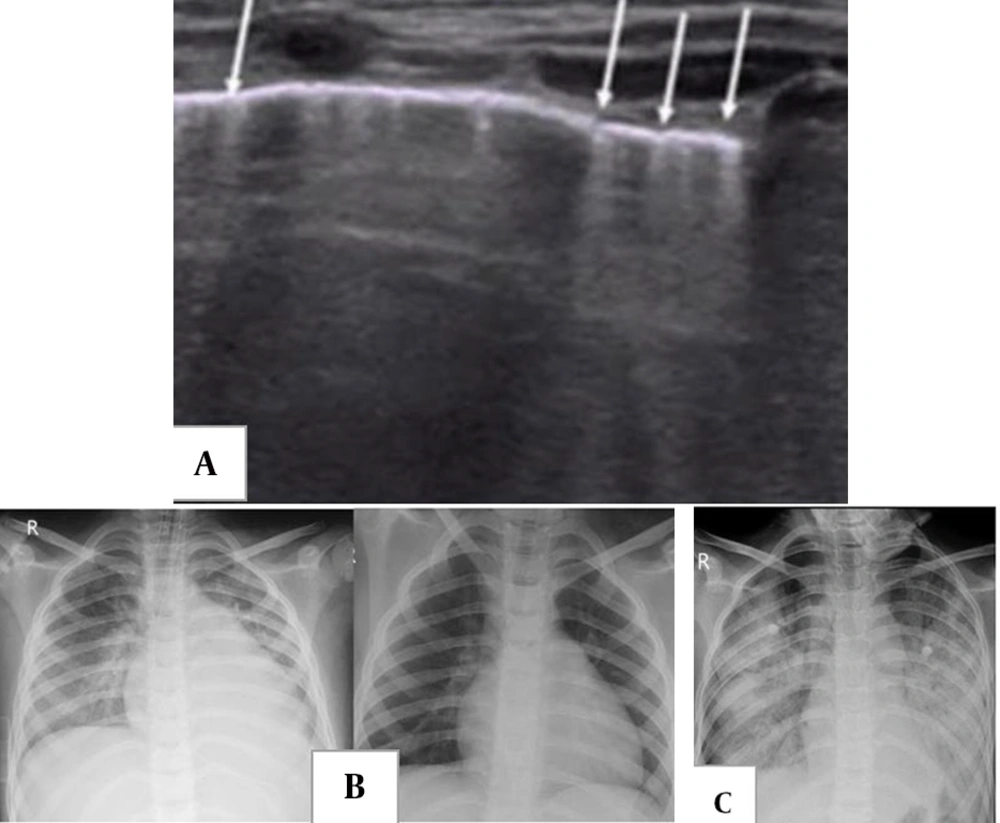

In adult COVID-19, lung US demonstrates B-lines and subpleural consolidations, often in the lower lobes (Figure 3A) (40). Pediatric COVID-19 cases show similar findings, indicating the utility of lung US, particularly given the typical peripheral lung involvement in children (26, 31, 42). However, the full role of lung US in pediatric COVID-19 requires further investigation (26).

A, two-week-old male full-term newborn with fever and mild respiratory symptoms; lung ultrasound (US) showed multiple vertical B-lines, from: Point-of-care lung US imaging in pediatric coronavirus disease 2019 (COVID-19); B, a 7-year-old boy initially presented with fever and abdominal pain, progressing to respiratory distress and shock; serology was positive for COVID-19. Chest X-ray (CXR) shows features of cardiogenic pulmonary edema, including cardiomegaly, perihilar interstitial thickening and haziness, and mild bilateral pleural effusion. Ten days after treatment and symptom resolution, only cardiomegaly remains due to left heart failure. C, acute respiratory distress syndrome (ARDS) in a 10-year-old boy with a diagnosis of multisystem inflammatory syndrome in children (MIS-C) with acute respiratory distress four weeks after acute COVID-19. Diffuse bilateral airspace consolidation is seen without cardiomegaly.

The main thoracic imaging findings in MIS-C (Table 2) include heart failure, an ARDS pattern, and pulmonary embolism. These present as cardiomegaly, cardiogenic pulmonary edema, and pleural effusions secondary to acute heart failure (Figure 3B and C) (5, 21, 40, 46-48). Initial CXRs in MIS-C are often normal (16).